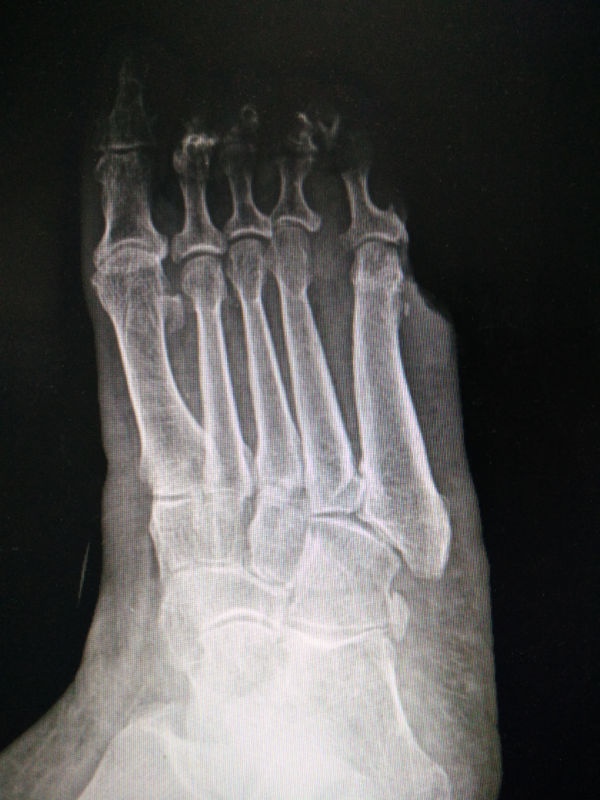

足正斜位x线正常图片,足斜位x线正常图片

足部x线解剖(足正位片)

足斜位x线正常图片

足正位x线正常图片

全足正位x线正常图片

右足正斜位片正常图片

正常足x线图片解剖图

正常足x线图片

足斜位x线解剖图

足正斜位片图片

足正常x线解剖图高清

正常的足部x光片图

足正斜位片

足部x线解剖图片